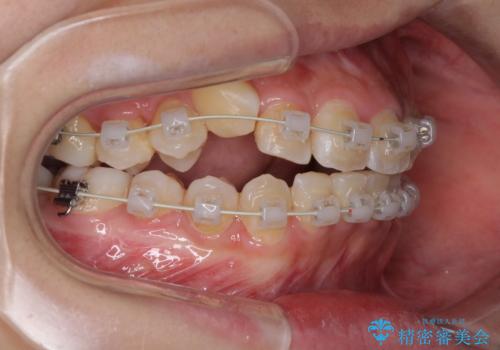

- 前歯のでこぼこと乳歯が残るほどの八重歯を気にして来院された患者様です。

非抜歯にてワイヤー矯正にて治療することとしました。(ただし、親知らずと乳歯は抜歯)

犬歯は歯根が太く長いため、移動には時間を要します。しかし、犬歯は機能面から考えて残すことを選択したいため、長期間をかけて治療を行うこととしました。

治療の度に歯列が改善していったため、長期間の治療も楽しく過ごしていいただき、満足のいく仕上がりとなりました。